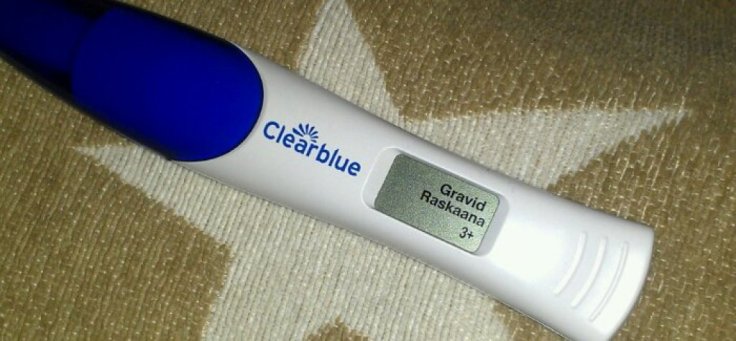

Jag säger det igen – vecka 17!

Mina närmsta kollegor på jobbet har nu fått ta del av ”nyheten” (som uppenbarligen är 17 veckor gammal). När jag sedan säger hur långt jag har gått så svarar flera förvånat: VA?!! SÅ långt??